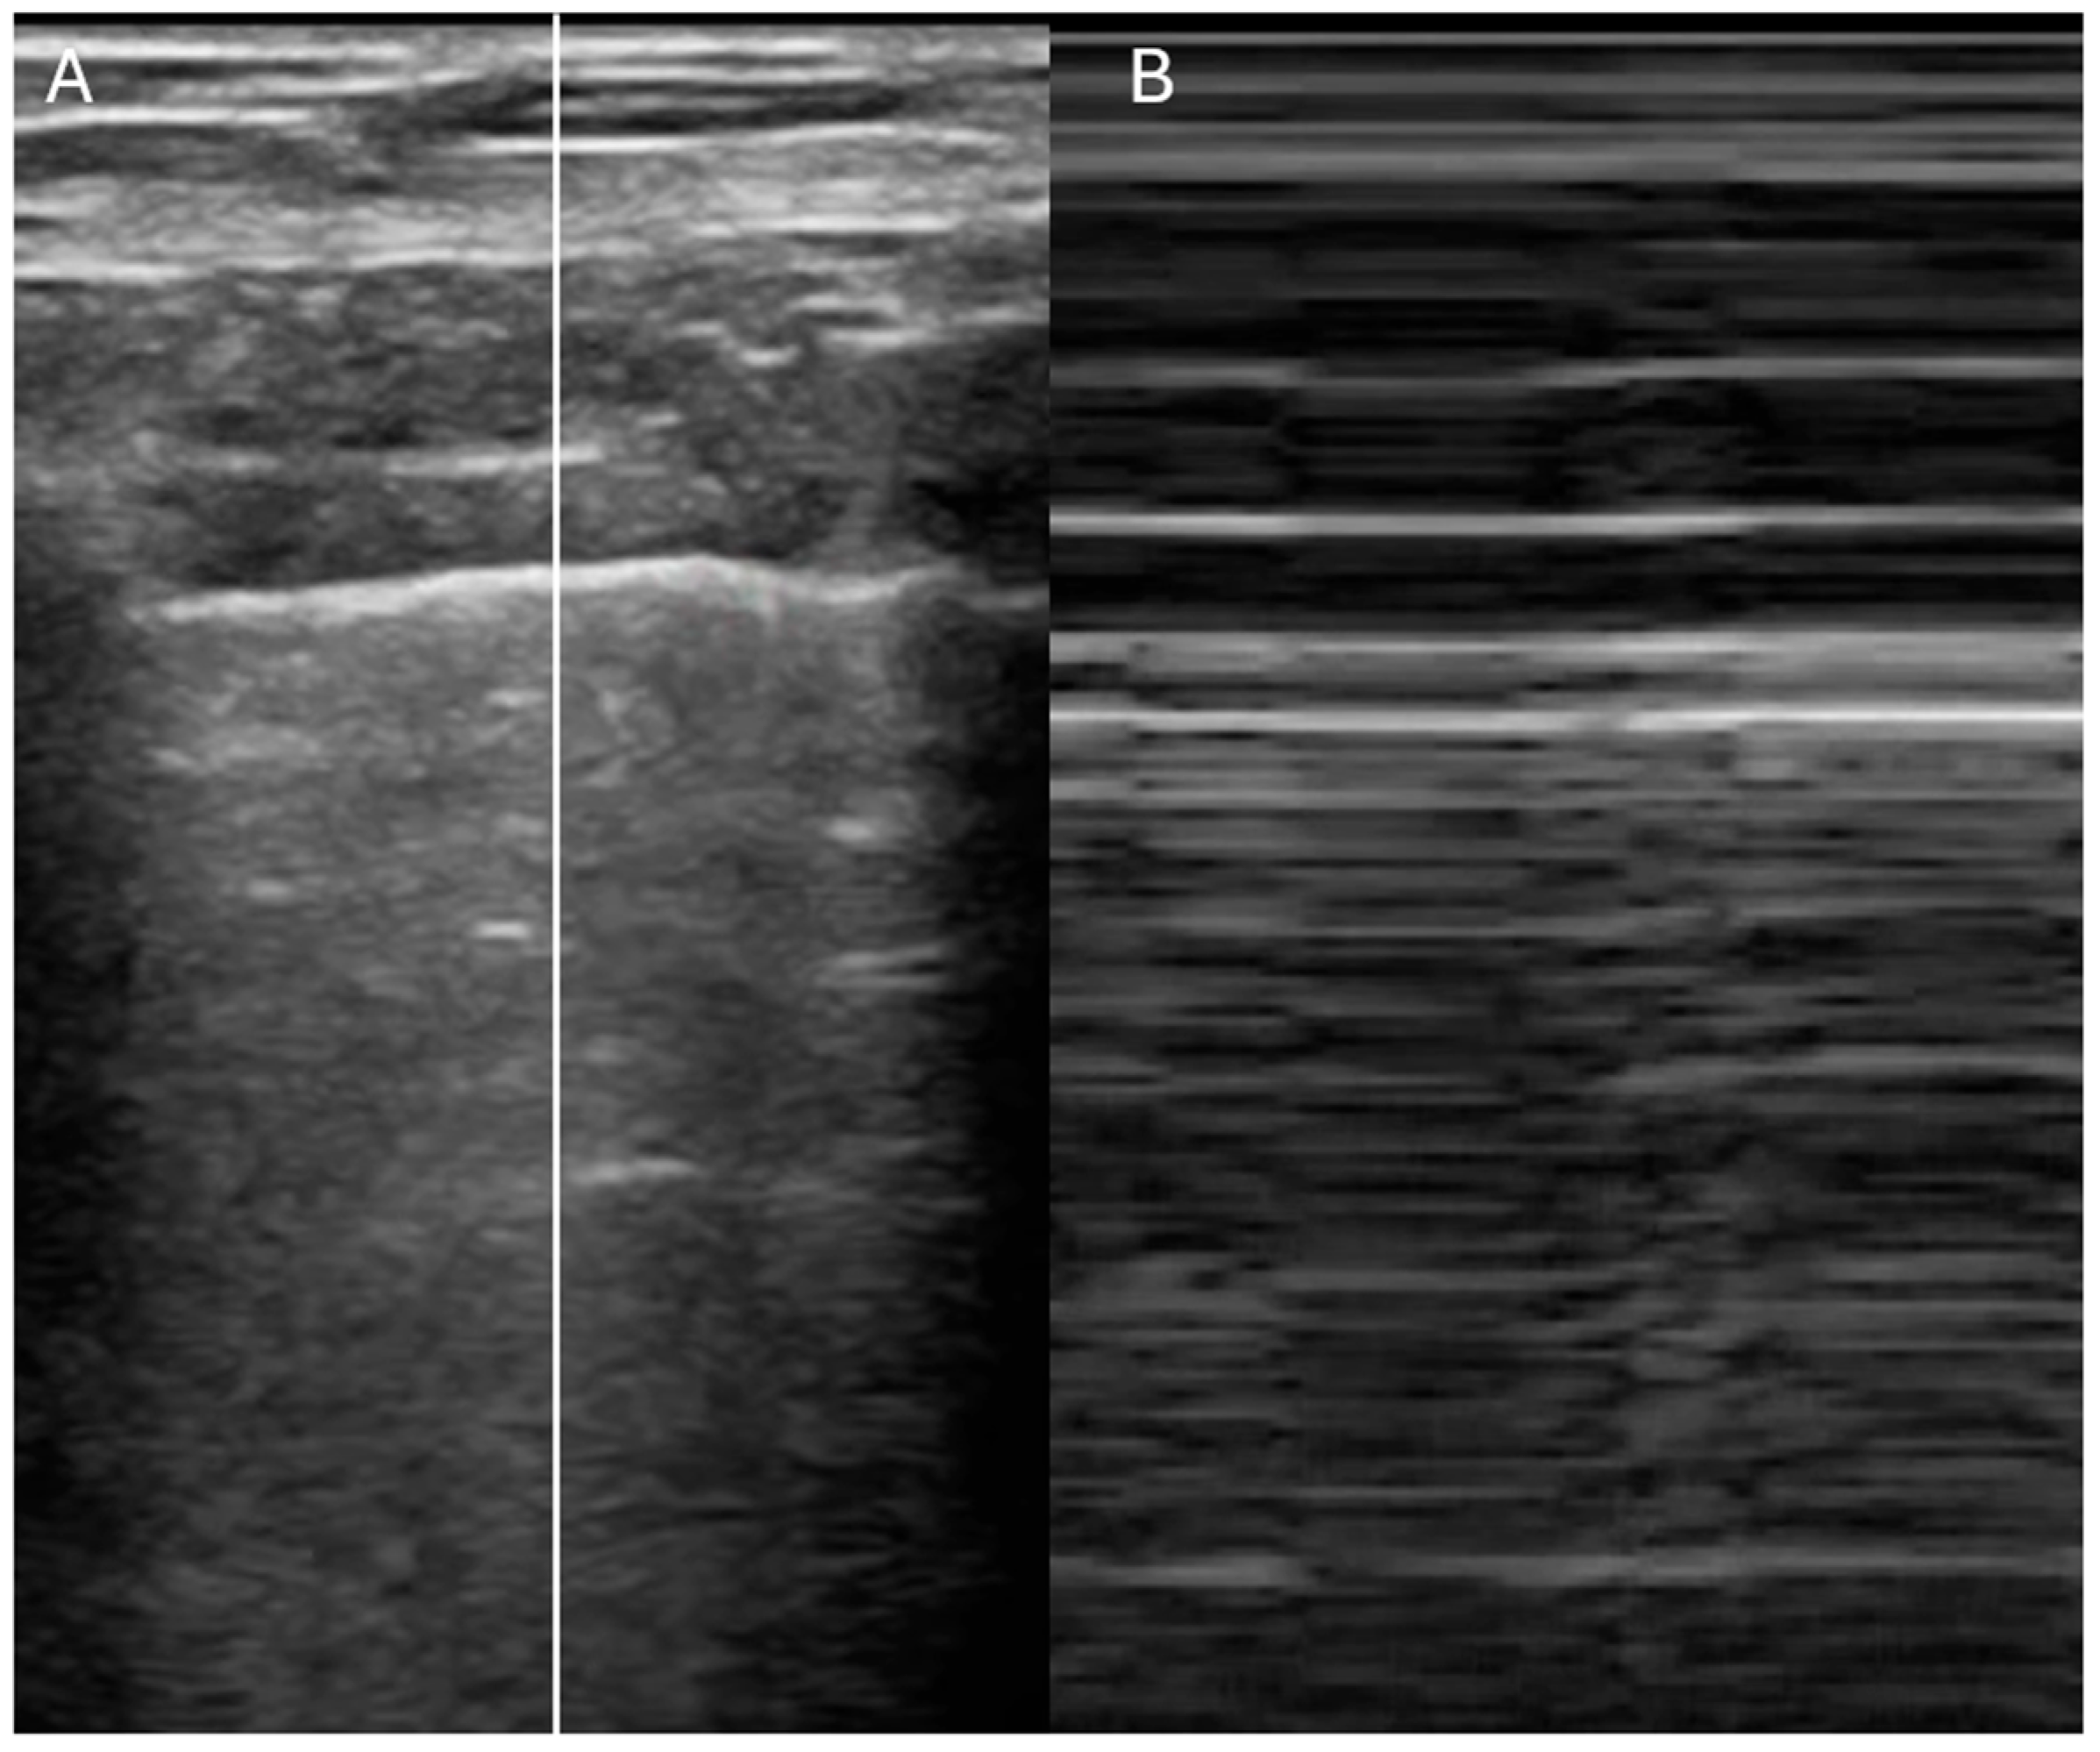

- Is the IVC dilated or collapsible?

- Assessment of right atrial pressure

- Ruge, M.; Marhefka, G.D. IVC measurement for the noninvasive evaluation of central venous pressure. J. Echocardiogr. 2022, 20, 133–143. [Google Scholar] [CrossRef]

- Rudski, L.G.; Lai, W.W.; Afilalo, J.; Hua, L.; Handschumacher, M.D.; Chandrasekaran, K.; Solomon, S.D.; Louie, E.K.; Schiller, N.B. Guidelines for the echocardiographic assessment of the right heart in adults: A report from the American Society of Echocardiography endorsed by the European Association of Echocardiography, a registered branch of the European Society of Cardiology, and the Canadian Society of Echocardiography. J. Am. Soc. Echocardiogr. 2010, 23, 685–713. [Google Scholar]

| IVC Diameter | Collapse with Sniff | Estimated RA Pressure |

|---|---|---|

| ≤2.1 cm | >50% | 0–5 mmHg |

| ≤2.1 cm | <50% | 5–10 mmHg |

| >2.1 cm | <50% | 10–20 mmHg |

| IVC diameter & collapsibility | Yes | Yes (with trending) | Yes (plus RA pressure estimate) |